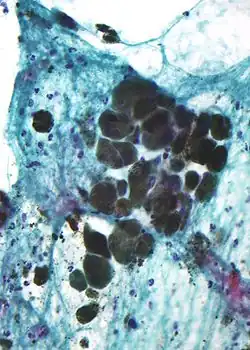

El albinismo oculocutáneo (OCA) es un desorden autosómico recesivo caracterizado por la hipomelanosis en la piel, en el cabello y en los ojos. El OCA se asocia con la agudeza visual reducida, nistagmo, estrabismo y fotofobia. La hipomelanosis se da debido a una deficiencia en la producción, en el metabolismo o en la distribución de melanina.[1] La producción de melanina se lleva a cabo en organelos intracelulares llamados melanosomas, que se encuentran dentro de un tipo especializado de células llamadas melanocitos. Variaciones en la secuencia de ADN, conocidas como polimorfismo de nucleótido único (SNP), donde se cambia una alanina por una treonina en la posición 111, dan como resultado distintos alelos en el gen SLC24A5.[12] Los melanosomas en los melanocitos de un paciente con mutaciones son menos maduros, en comparación con los melanosomas de un paciente sano, lo cual sugiere que la proteína codificada por el gen se requiere en la membrana de los melanocitos para la maduración de los melanosomas, lo que conlleva a la producción óptima de melanina.[17]